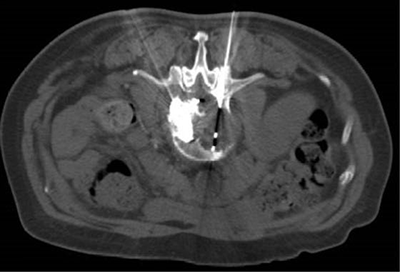

(腸梗阻導(dǎo)管植入術(shù))(DSA引導(dǎo)下骨水泥注射椎體成形術(shù))

(骨惡性腫瘤的消融治療) (CT引導(dǎo)下骨水泥注射椎體成形術(shù)及粒子植入術(shù))